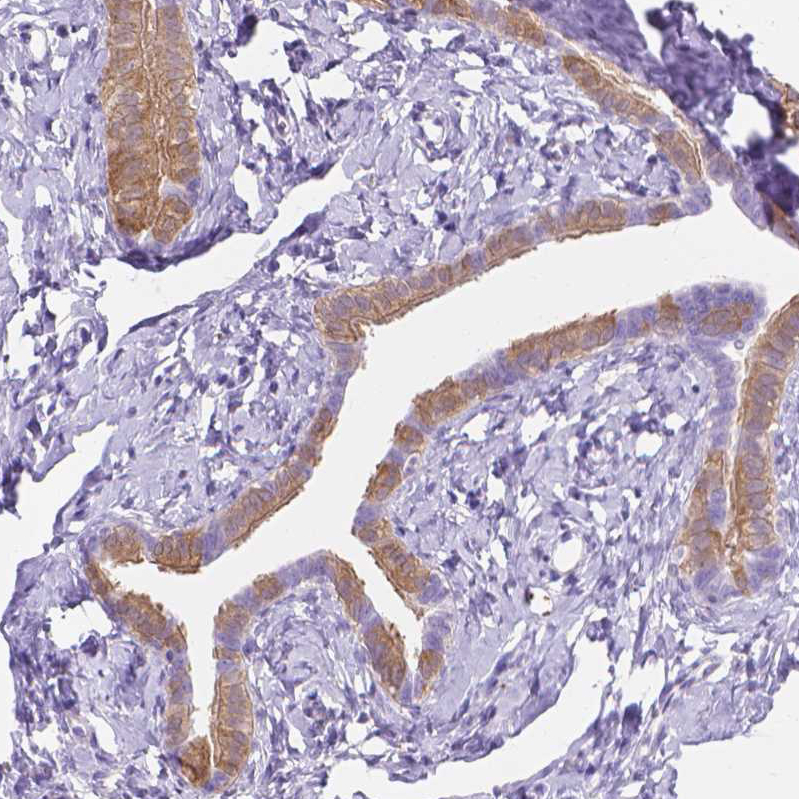

Immunohistochemical staining of human endometrium shows moderate membranous positivity in a subset of glandular cells.